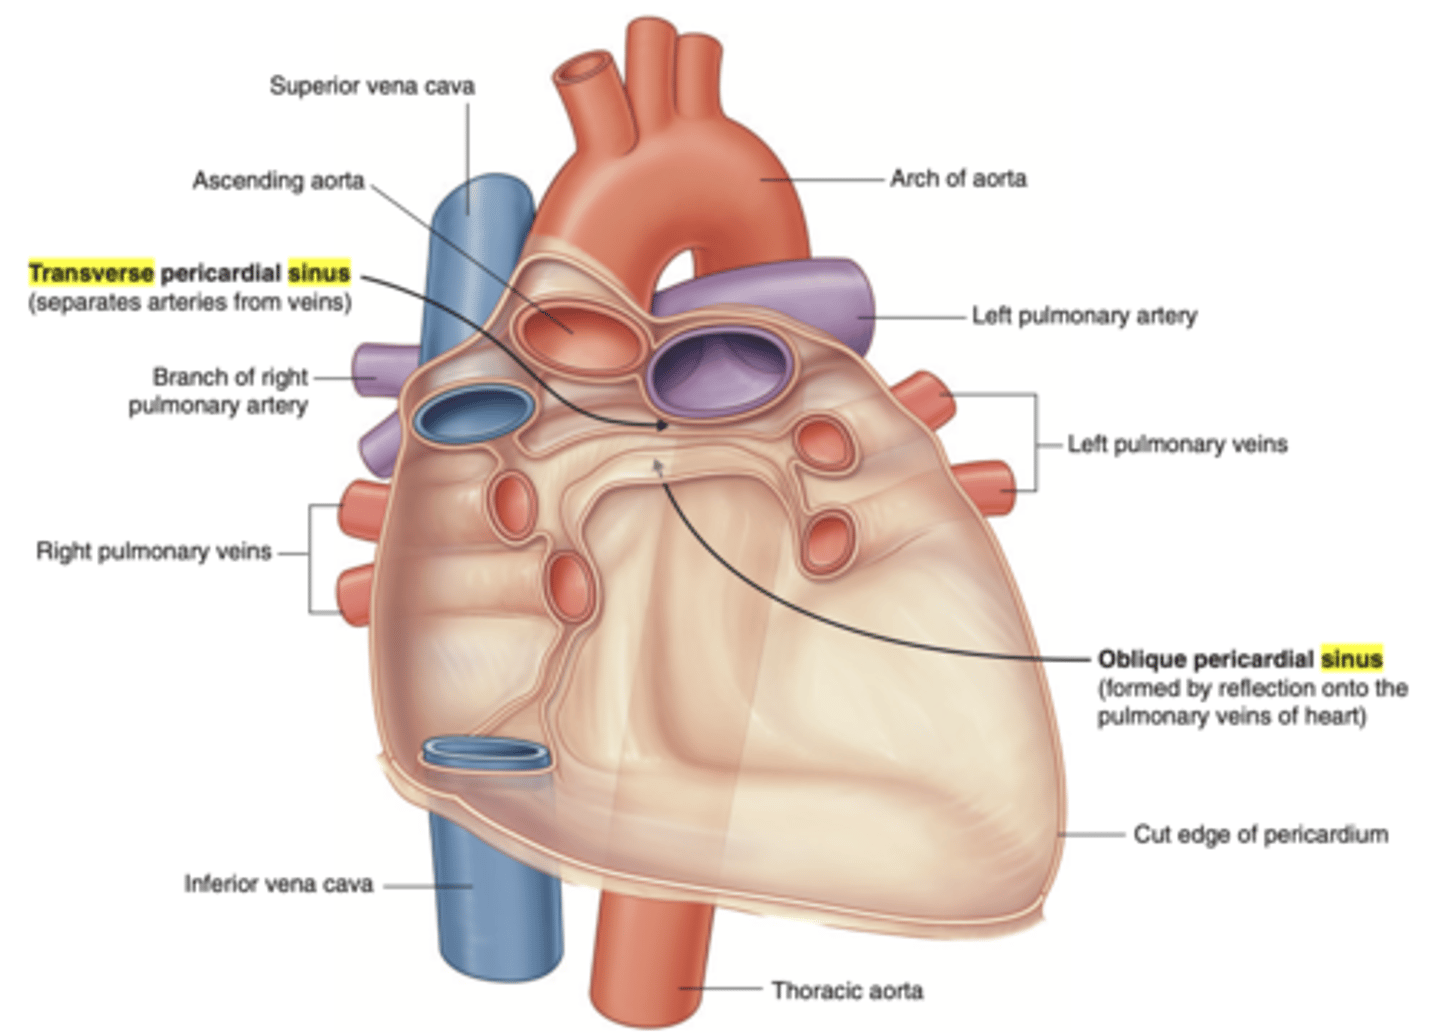

What are the pericardial sinuses and their relevance?

. transverse sinus

. oblique sinus

. Allow for the passage of structures such as blood vessels

. Clinically significant as potential sites of fluid accumulation.

What is the transverse sinus of the pericardium ?

. space posterior to the aorta and pulmonary trunk

. anterior to vena cava

EMBRIOLOGICALLY COMES FROM THE DISINTEGRATION OF THE DORSAL MESOCARDIUM

Clinical significance of the transverse sinus?

Surgeons use it during cardiac procedures.

By passing a finger or clamp through the sinus they can isolate these arteries and control blood flow to the heart during surgeries like coronary artery bypass grafting (CABG).

What is the oblique sinus of the pericardium?

Area where the parietal pericardium reflects (transition) into the visceral pericardium.

Posterior to the heart, cradled by the left atrium and the pulmonary veins.